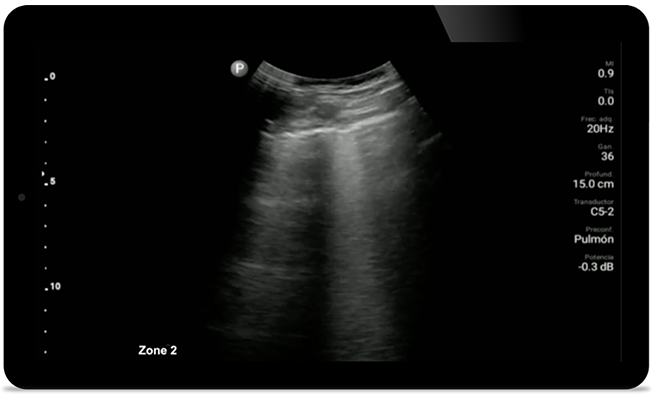

Genau hinsehen bei COVID- Pneumonie

Ähnlich einem Thorax-CT kann Lumify bei der Diagnose und Beurteilung von Pneumonie oder Atemnotsyndrom von Erwachsenen helfen.